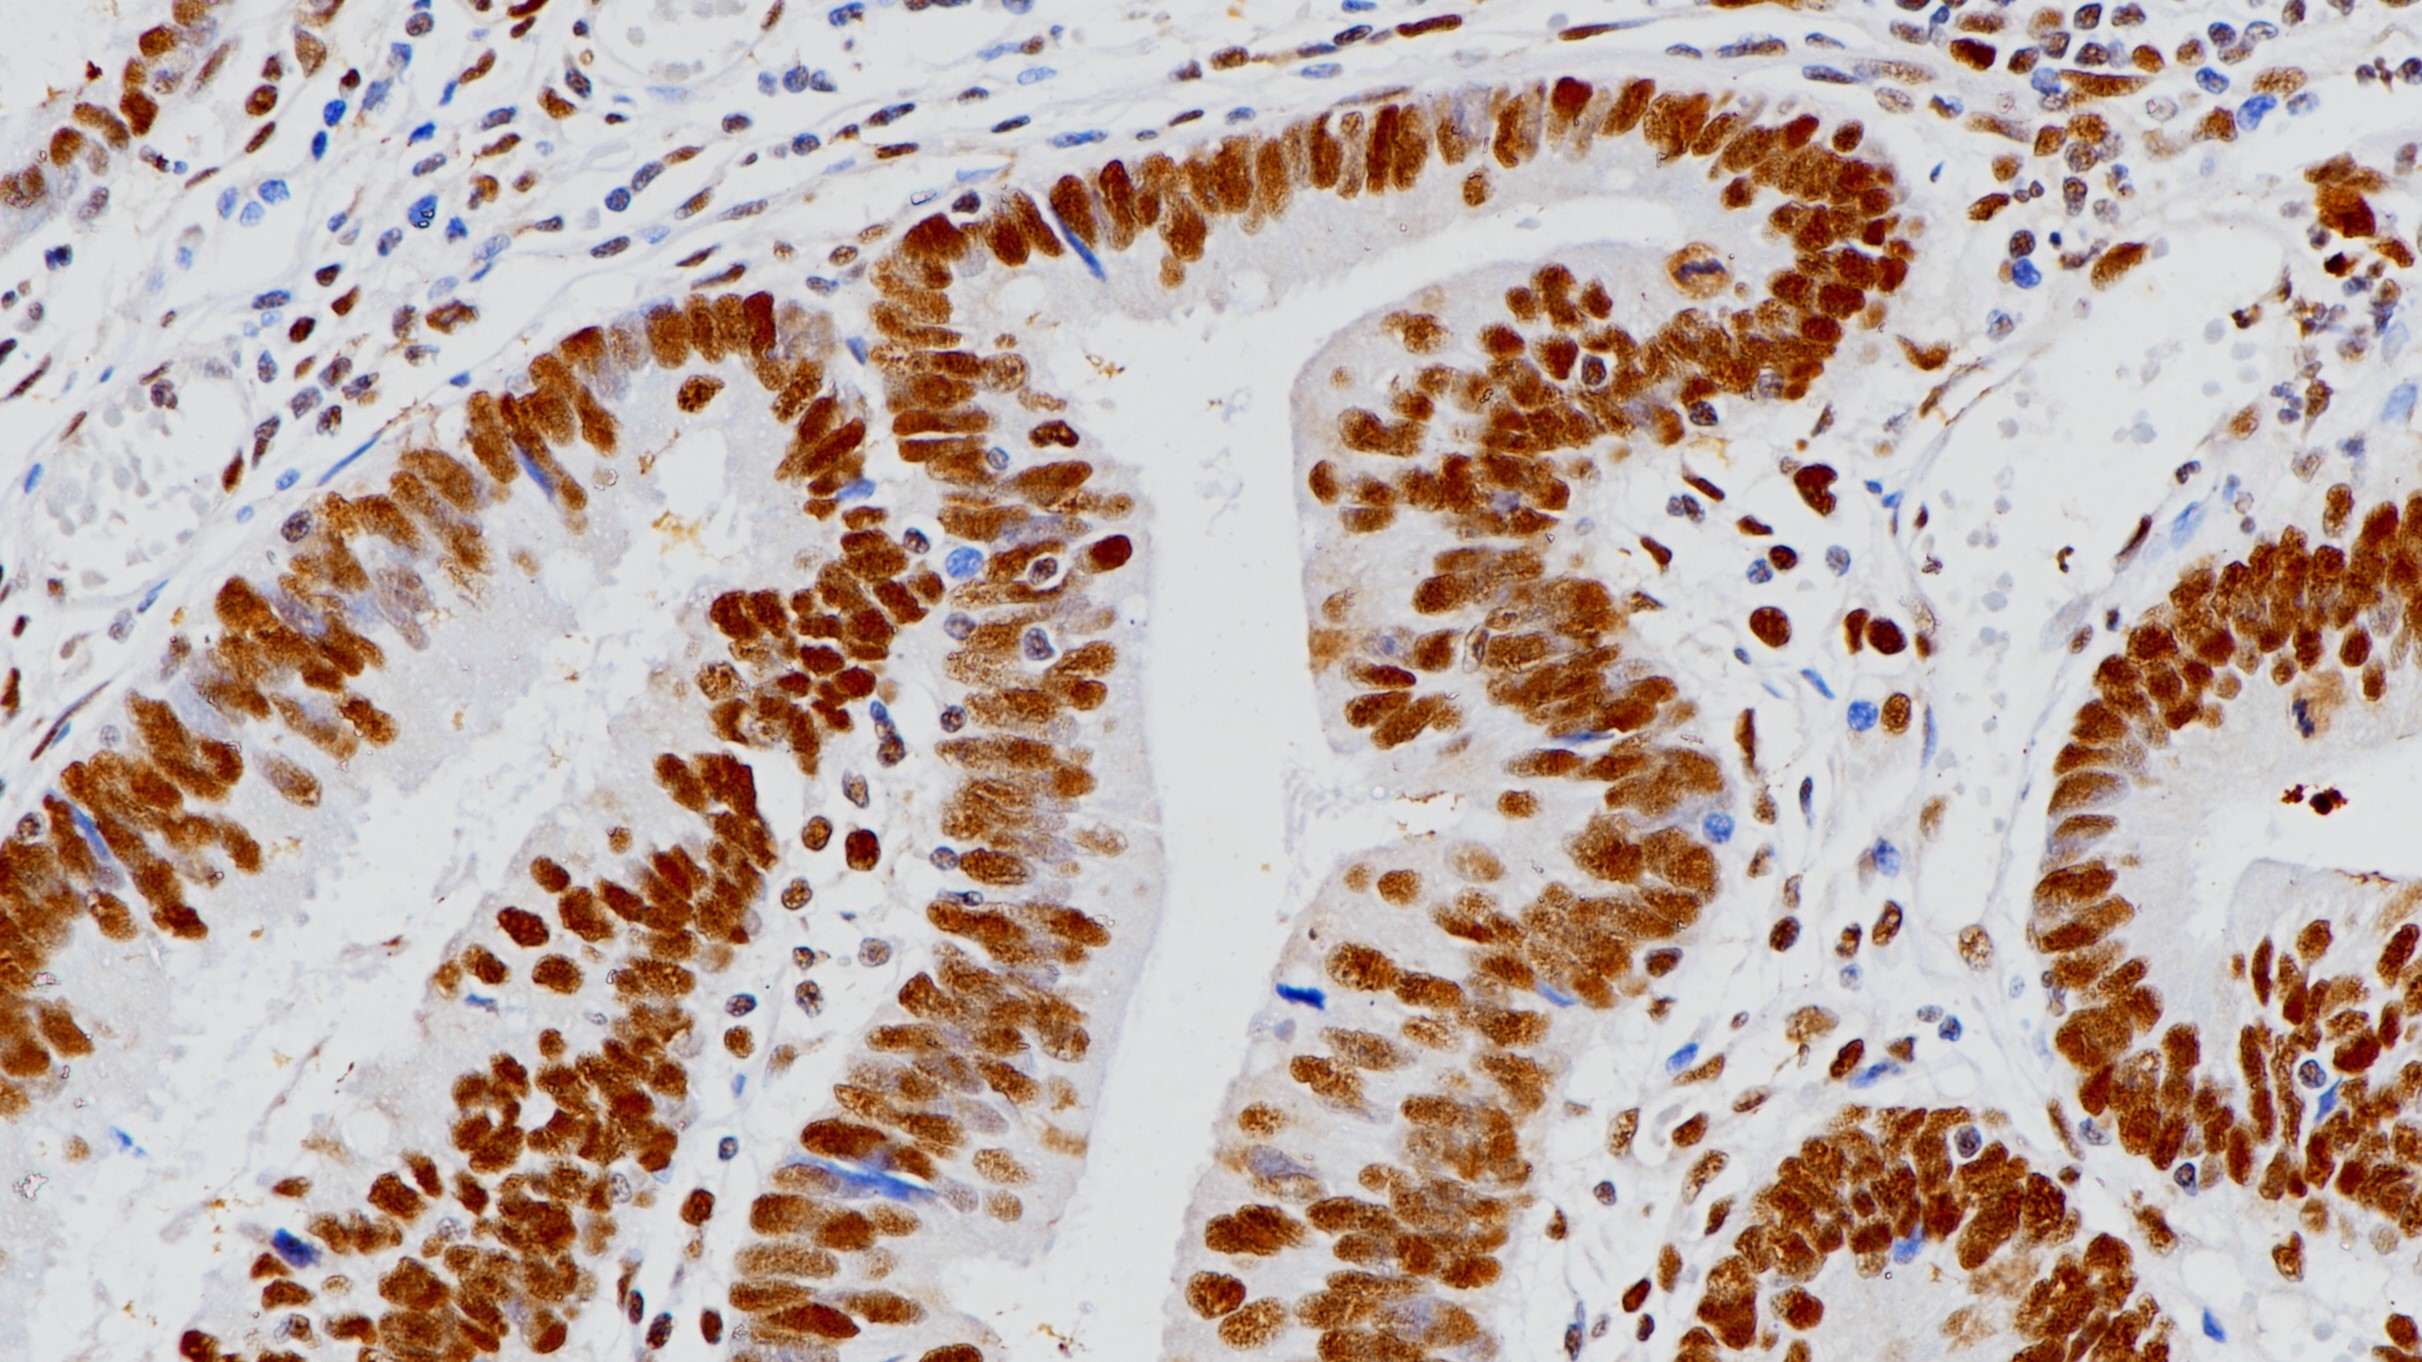

2.钟璧璟,雷芹.结直肠癌患者MLH1、MSH2、MSH6、PMS2蛋白的表达水平及其与淋巴转移的相关性[J].海南医学,2020,31(03):287-290.